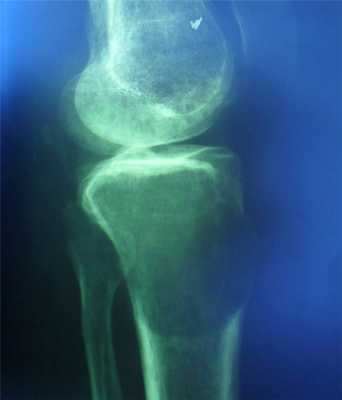

Гигантоклеточная опухоль

(остеобластокластома)

- состоит из клеток 2 типов- многоядерных гигантских и мелких одноядерных,

- поражаются люди в возрасте от 20 до 40 лет,

- локализация бедренная кость - дистальный конец, проксимальный конец б/берцовой кости, дистальный конец лучевой кости. Из плоских костей - тазовые кости и лопатка, очень редкая локализация в позвонках,

- одиночность и изолированность поражения,

- характерно расположение опухоли в эпиметафизраном отделе, который значительно вздут и деформирован, имеет вид крупнобугристого полушария, булавы,

- опухоль доходит до суставного хряща и обрывается,

- растет во всех направлениях, но главный рост происходит вдоль длинной оси кости в сторону с/3 диафиза кости,

- поперечник опухоли может увеличивать нормальный диаметр опухоли в 3-5 раз.

- ячеистый тип - опухоль состоит из отдельных камер, отделенных друг от друга полными и неполными перегородками (мыльные пузыри или неправильные соты),

- корковое вещество раздвигается, вздувается изнутри, истончается, надкостничных наслоений нет,

- при больших опухолях корковое вещество рассасывается и опухоль окружена со всех сторон тонкой скорлупой состоящая из стенок поверхностно расположенных ячеек.

- остеолитический тип - полное отсутствие ячеистого или трабекулярного рисунка, дефект кости вполне гомогенен,

- краевой блюдцеобразный дефект,

- корковый слой на пораженном месте рассасывается, а на границе с дефектом корка заострена, не подрыта и не имеет никаких периостальных наслоений,

- контуры дефекта резкие,

- патологические переломы в 12% случаев.